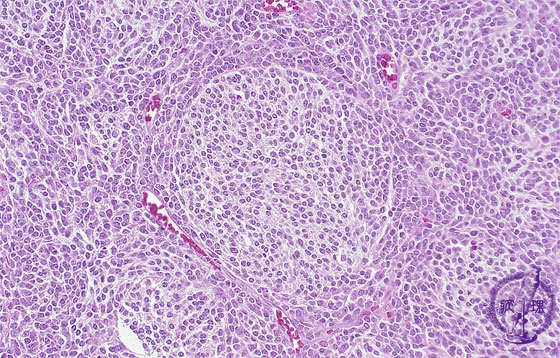

- (14)Medulloblastoma

Micro H&E; The nodular desmoplastic variant. The tumor composed of areas of stromal response, pale islands, and surrounded by areas of high cellularity (dark area).